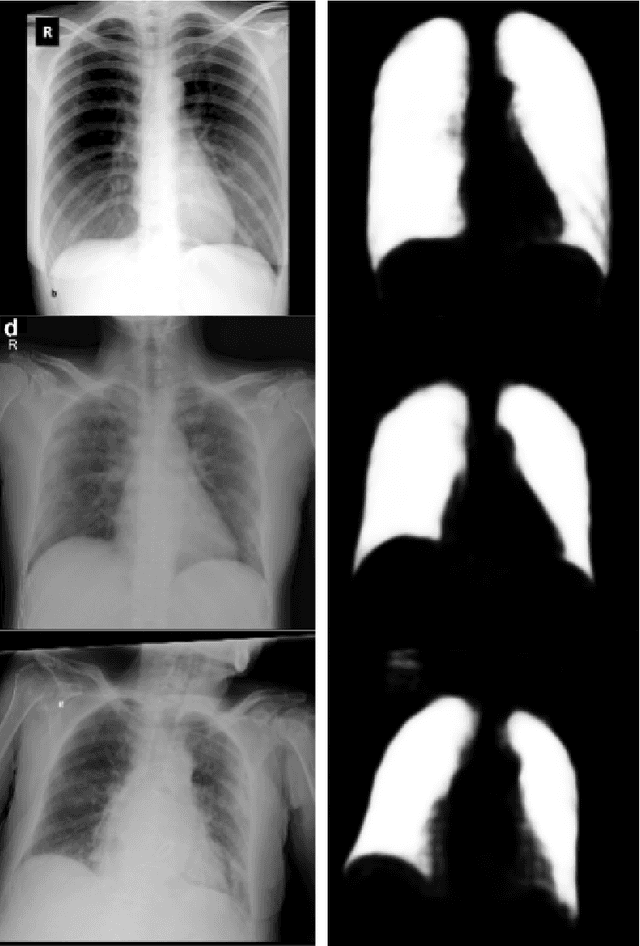

Abstract:We evaluated the generalization capability of deep neural networks (DNNs), trained to classify chest X-rays as COVID-19, normal or pneumonia, using a relatively small and mixed dataset. We proposed a DNN architecture to perform lung segmentation and classification. It stacks a segmentation module (U-Net), an original intermediate module and a classification module (DenseNet201). We compared it to a DenseNet201. To evaluate generalization, we tested the DNNs with an external dataset (from distinct localities) and used Bayesian inference to estimate the probability distributions of performance metrics, like F1-Score. Our proposed DNN achieved 0.917 AUC on the external test dataset, and the DenseNet, 0.906. Bayesian inference indicated mean accuracy of 76.1% and [0.695, 0.826] 95% HDI with segmentation and, without segmentation, 71.7% and [0.646, 0.786]. We proposed a novel DNN evaluation technique, using Layer-wise Relevance Propagation (LRP) and the Brixia score. LRP heatmaps indicated that areas where radiologists found strong COVID-19 symptoms and attributed high Brixia scores are the most important for the stacked DNN classification. External validation showed smaller accuracies than internal validation, indicating dataset bias, which segmentation reduces. Performance in the external dataset and LRP analysis suggest that DNNs can be trained in small and mixed datasets and detect COVID-19.

Abstract:We present an image classifier based on the CheXNet and a transfer learning stage to classify chest X-Ray images according to three labels: COVID-19, viral pneumonia and normal. CheXNet is a DenseNet121 that has been trained twice, firstly on ImageNet and then, for classification of pneumonia and other 13 chest diseases, over a large chest X-Ray database (ChestX- ray14). The proposed network reached a test accuracy of 97.8% and, for the COVID-19 class, of 98.3%. In order to clarify the modus operandi of the network, we used Layer Wise Relevance Propagation (LRP) to generate heat maps, indicating an analytical path for future research on diagnosis.